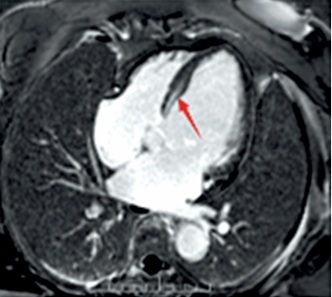

A case study of a classic cardiac phenotype resulting from a rare missense mutation in the LMNA gene is presented to underscore the vital significance of comprehensive genetic assessment in the context of specific clinical manifestations. The patient, a 67-year-old woman, was hospitalized in May 2025 due to a one-month history of “paroxysmal palpitations with associated dizziness and weakness”. Of particular note was her family history: her mother succumbed to coronary artery disease, and notably, her 10-year-old granddaughter had experienced recurrent unexplained syncopal episodes, strongly indicating a potential hereditary predisposition across generations. On admission examination, the cardiac border was found enlarged to the left and downward. Occasional premature contractions were heard on auscultation. Holter monitoring revealed frequent non-sustained ventricular tachycardia (NSVT) (83 episodes/24 h), marked heart rate variability (maximum 210 bpm, minimum 38 bpm), and sinus pauses (longest 2.8 s), consistent with the typical arrhythmic phenotype of LMNA-related cardiomyopathy. The coexistence of atrioventricular conduction abnormalities and ventricular arrhythmias represents an important marker of a sudden cardiac death risk in patients with LMNA variants, and constitutes a clear indication for implantable cardioverter-defibrillator (ICD) implantation. Cardiac ultrasound demonstrated marked left ventricular enlargement, a blunted apical cone, diffuse and dyssynchronous wall motion, and significantly impaired left ventricular systolic function (LVEF approximately 35%), the right ventricle was normal in size (RV 18 mm, RVOT 28 mm) and function. To precisely quantify the cardiac structure and function and investigate the etiology, the patient had cardiac magnetic resonance (CMR) imaging performed. As shown in Figure 1, CMR imaging demonstrated a marked left ventricular dilatation with a severely reduced global systolic function. The key finding was patchy mid-myocardial late gadolinium enhancement (LGE) involving the left ventricular apex and lateral wall, comprising approximately 15% of left ventricular myocardial mass, with a non-ischemic distribution pattern consistent with myocardial fibrosis. To comprehensively rule out coronary artery disease – the most common cause of left ventricular dysfunction – and confirm the diagnosis of non-ischemic cardiomyopathy, the patient underwent coronary angiography, which revealed non-obstructive coronary artery disease (CAD) with all stenoses < 50%. This finding definitively ruled out clinically significant obstructive coronary artery disease. Given the patient’s presentation of “dilated cardiomyopathy with high-burden ventricular tachycardia and conduction abnormalities (frequent premature ventricular contractions)” and a family history of syncope in younger relatives, hereditary cardiomyopathy – particularly laminoproliferative disease – was highly suspected clinically. Following informed consent, peripheral blood was collected and subjected to next-generation sequencing using a hereditary cardiomyopathy/arrhythmia-related gene panel (Version V3). Genetic analysis revealed a heterozygous missense mutation in exon 3 of the LMNA gene: c.565C>T (p.Arg189Trp), as detailed in Table I. This variant causes substitution of arginine at position 189 with tryptophan in the encoded protein. According to the American College of Medical Genetics and Genomics guidelines [1], this variant is classified as likely pathogenic based on the following rationale: the site exhibits high conservation across multiple species; arginine is a crucial polar amino acid, and its replacement with the hydrophobic tryptophan is predicted to adversely affect protein structure/function; the mutation exhibits extremely low frequency in normal population databases; it demonstrates high concordance with the patient’s phenotype (clear features of LMNA-related cardiac pathology).